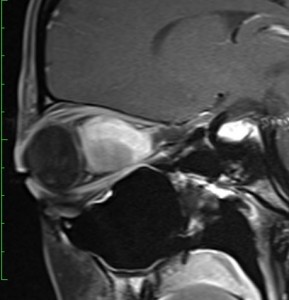

18歳で発症して,60歳まで無治療の大きな視床下部毛様細胞性星細胞腫

hypothalamic pilocytic astrocytoma

1968年 18歳の時に頭痛嘔吐で発症しました。第3脳室腫瘍と閉塞性水頭症の診断だけで,シャント手術を受けました。手術も化学療法も放射線治療もされていません。下の画像は60代で撮影されたものです。この例では,第3脳室内に増大した大きな毛様細胞性星細胞腫が,視床下部下垂体障害を出すことなく,自然経過で増大停止 growth arrest して,カチカチに固まってしまうということを教えてくれます。でも,こんなに都合よく経過観察できる例も珍しいです。

CTでは強い石灰化があります。右のT2強調画像では腫瘍は等信号,視交叉の後ろにあります。内部の低信号は石灰化です。

T1強調画像では等信号,ガドリニウム増強でごく一部がまだらに増強されます。